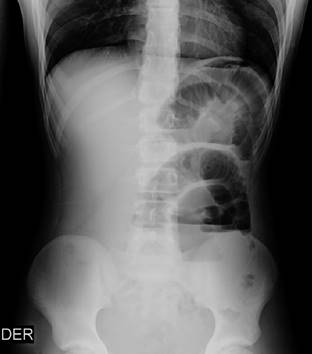

Las radiografías de abdomen con asas de intestino delgado dilatadas con presencia de niveles hidroaéreos (Figura 1).